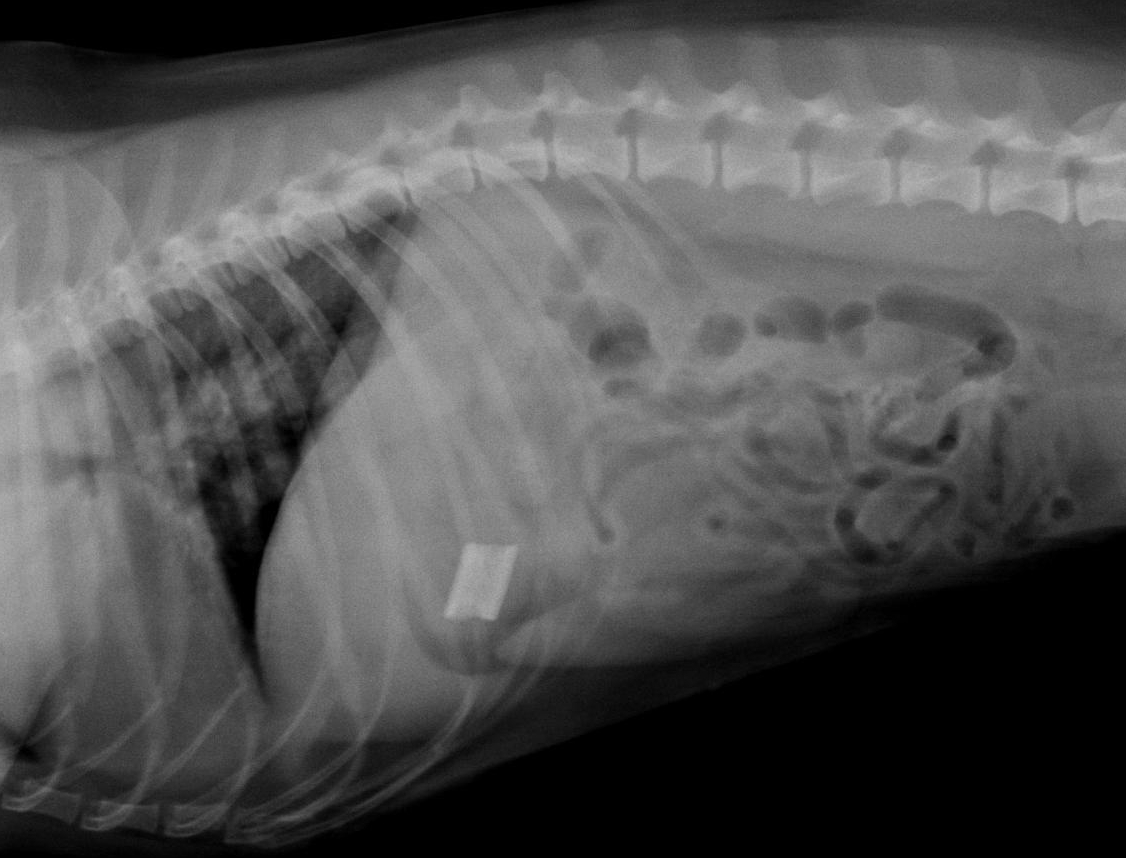

DILATACIÓN ESTOMACAL

La causa de la DILATACIÓN/VÓLVULO ESTOMACAL se desconoce pero puede derivar de una motilidad gástrica anormal. La conformación del tórax guarda relación con el riesgo; el Setter irlandés con un tórax más profundo en relación con el ancho, tiene mayor probabilidad de experimentar DVE. Los perros cuyos padres sufrieron el proceso pueden tener el riesgo de padecerlo. Existen datos contradictorios con respecto a la influencia del sexo y la rapidez en la ingestión de la comida, pero parece ser que la ingestión de la ración del día en una sola vez, y la exposición posterior al ejercicio, pueden incidir de manera significativa en su aparición.

La DVE ocurre cuando el estómago se dilata de forma excesiva con gas. El estómago puede mantener su posición anatómica normal (dilatación gástrica) o darse la vuelta, es decir, retorcerse (DVE). Si el estómago se retuerce lo suficiente, la salida del estómago (píloro) se obstruye y se produce la distensión gaseosa progresiva, es decir, el estómago se va llenando de aire. La torsión del bazo puede ocurrir en forma concurrente. La distensión gástrica masiva obstruye las venas porta hepática y cava posterior, causando serios transtornos circulatorios.

Podemos decir que la DVE se presenta principalmente en razas caninas grandes y gigantes con tórax profundo; rara vez la veremos en razas pequeñas y medianas.

Los perros afectados presentarán arcadas improductivas y manifestarán dolor abdominal. Al poco tiempo, si observamos el abdomen del perro, veremos una importante distensión, aunque no siempre se hace evidente en perros grandes y musculados. Eventualmente se observará depresión y un estado moribundo.

Las radiografías laterales del lado derecho del abdomen del perro, nos permitirán el diagnóstico de este grave proceso.

El tratamiento consiste en una terapia agresiva para contrarrestar el estado de choque en que se encuentran estos animales, y debe empezar con la infusión de una solución salina hipertónica, que debe ser seguida de la descompresión estomacal (sacar el aire del estómago), a no ser que el paciente se esté asfixiando, en cuyo caso lo primero que hay que hacer es actuar a nivel del estómago.

La descompresión se hará con un tubo orogástrico, y posteriormente se hará un lavado del estómago con agua templada. Si el tubo no entra en el estómago con facilidad, se optará por una punción del mismo con un trocar adaptado para tal fin o bien por medio de una gastrotomía.

Una vez estabilizado el perro, se procederá de forma quirúrgica, para recolocar el estómago, y extirpar el bazo si es que ha sufrido daños irreparables. En ocasiones se puede optar por intervenir mediante cirugía antes de estabilizar al perro, previa descompresión estomacal, según la valoración clínica que se haya realizado.

El pronóstico depende de la rapidez del reconocimiento del proceso y de su oportuno tratamiento. Se han comunicado tasas de mortalidad del 30%.